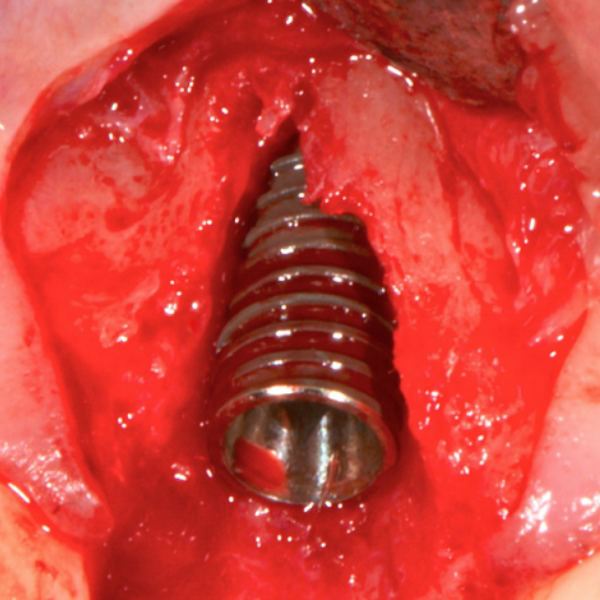

Anterior Implant Placement & Graft